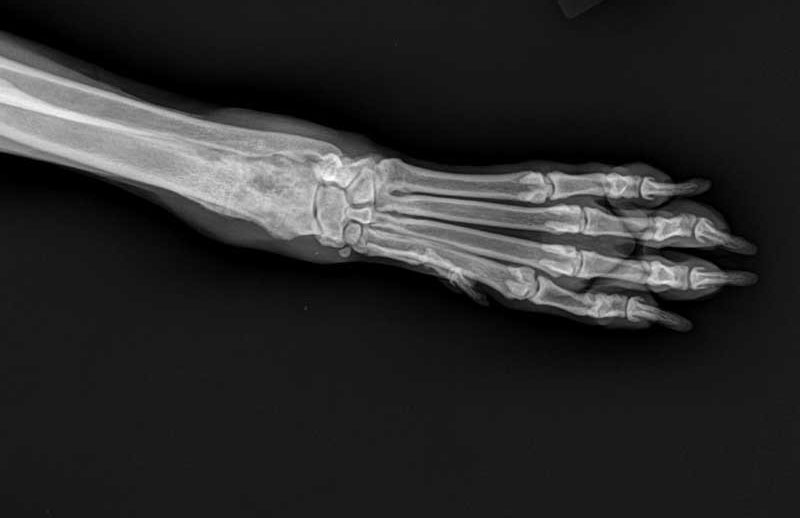

Osteosarcoma of the radius in an eight-year-old Labrador.